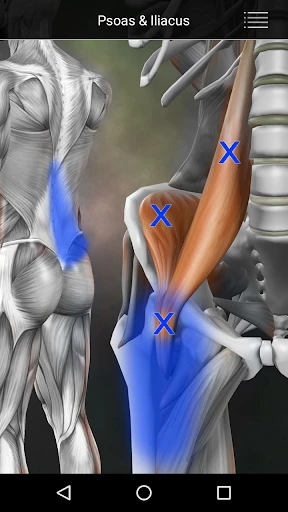

The app launches you into a detailed map of the human body, highlighting key muscle groups and their potential trigger points. This is perfect for anyone keen on learning more about their anatomy, whether you’re a seasoned athlete or just someone looking to relieve some tension. The interface is clean and intuitive, making it easy to navigate through the complex web of musculature.

What I really enjoyed about this app is the interactive element. You can tap on different muscle groups to see common trigger points, and it provides detailed descriptions of each. This isn’t just a static anatomy chart; it’s like having a mini anatomy lesson in your pocket. Plus, the app includes helpful tips on how to alleviate discomfort in these areas, which I found quite practical.